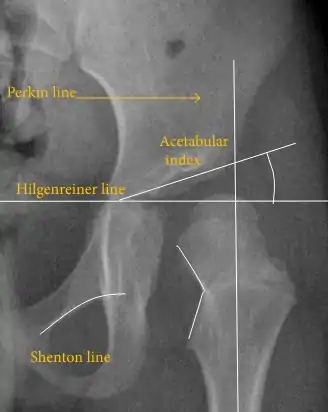

The most useful lines and angles that can be drawn in the pediatric pelvis assessing hip dysplasia are as follows:[45] Different measurements are used in adults.[45]